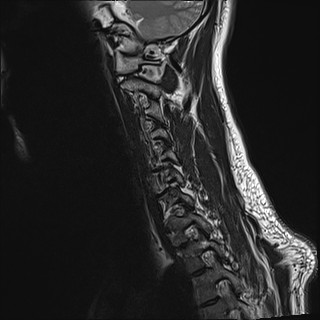

Wirbelsäule HWS

t2_tse_sag